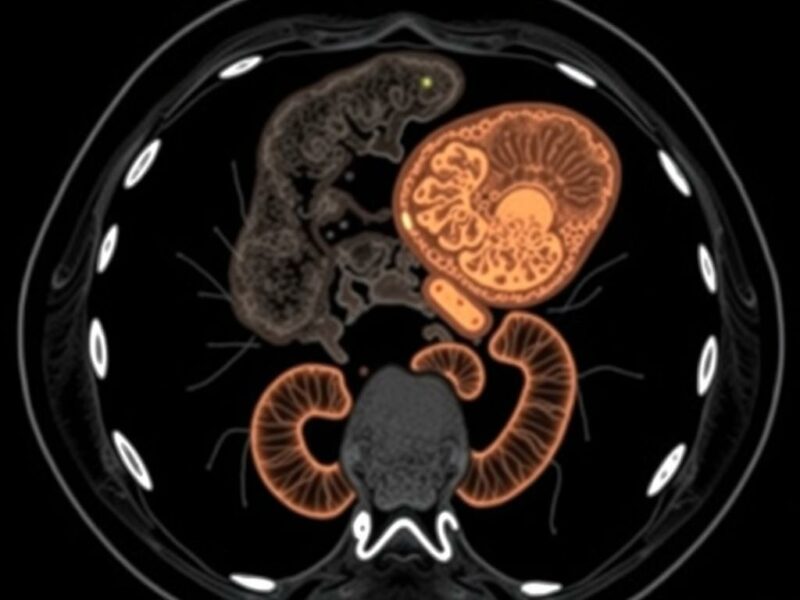

Cuando hablamos de IA en imágenes médicas nos referimos a un conjunto de técnicas que incluyen desde algoritmos clásicos de aprendizaje automático hasta redes neuronales profundas (deep learning). En el contexto de la TC abdominal para apendicitis, las tareas típicas que la IA aborda son la segmentación (localizar y delimitar el apéndice), la clasificación (decidir si hay apendicitis) y la detección de complicaciones (absceso, perforación, obstrucción intestinal asociada).

Las redes convolucionales (CNN) son las arquitecturas dominantes para imágenes: aprenden características directamente de los píxeles y pueden distinguir texturas, bordes y patrones complejos. Modelos más avanzados combinan CNN con enfoques de atención para centrar el análisis en regiones relevantes o usan redes 3D que procesan volúmenes completos de TC para conservar información espacial. Otra estrategia complementaria es la radiómica, que extrae cientos de características cuantitativas de las imágenes (formas, texturas, intensidad) y las usa en modelos estadísticos o máquinas de soporte vectorial. En la práctica clínica emergente, lo habitual es ver soluciones híbridas que combinan segmentación automática del apéndice, extracción radiómica y clasificación con redes profundas.

Un flujo típico de IA integrado en el proceso de lectura tomográfica puede incluir los siguientes pasos: preprocesado de la imagen (normalización, eliminación de artefactos), detección automática de la región abdominal relevante, segmentación del apéndice, cálculo de métricas (diámetro, grosor de pared, realce), evaluación de signos periapendiculares y, finalmente, una clasificación probabilística que sugiere la presencia o ausencia de apendicitis y su posible complicación. Este resultado se presenta al radiólogo dentro del visor de imágenes, enfatizando hallazgos y proponiendo métricas que el clínico puede revisar y aceptar o refutar.